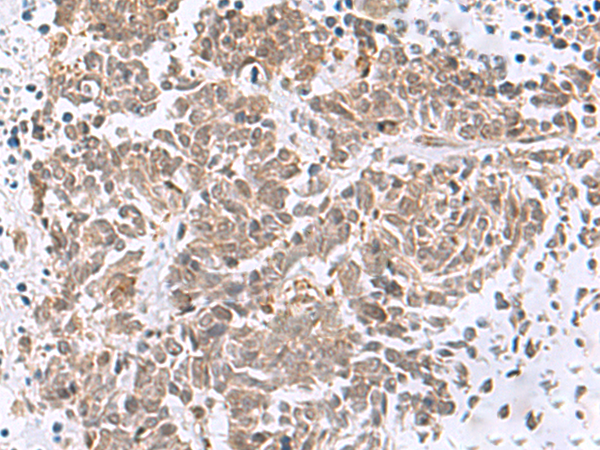

The image is immunohistochemistry of paraffin-embedded Human lung cancer tissue using (RBFOX2 Antibody) at dilution 1/50. (Original magnification: ×200)